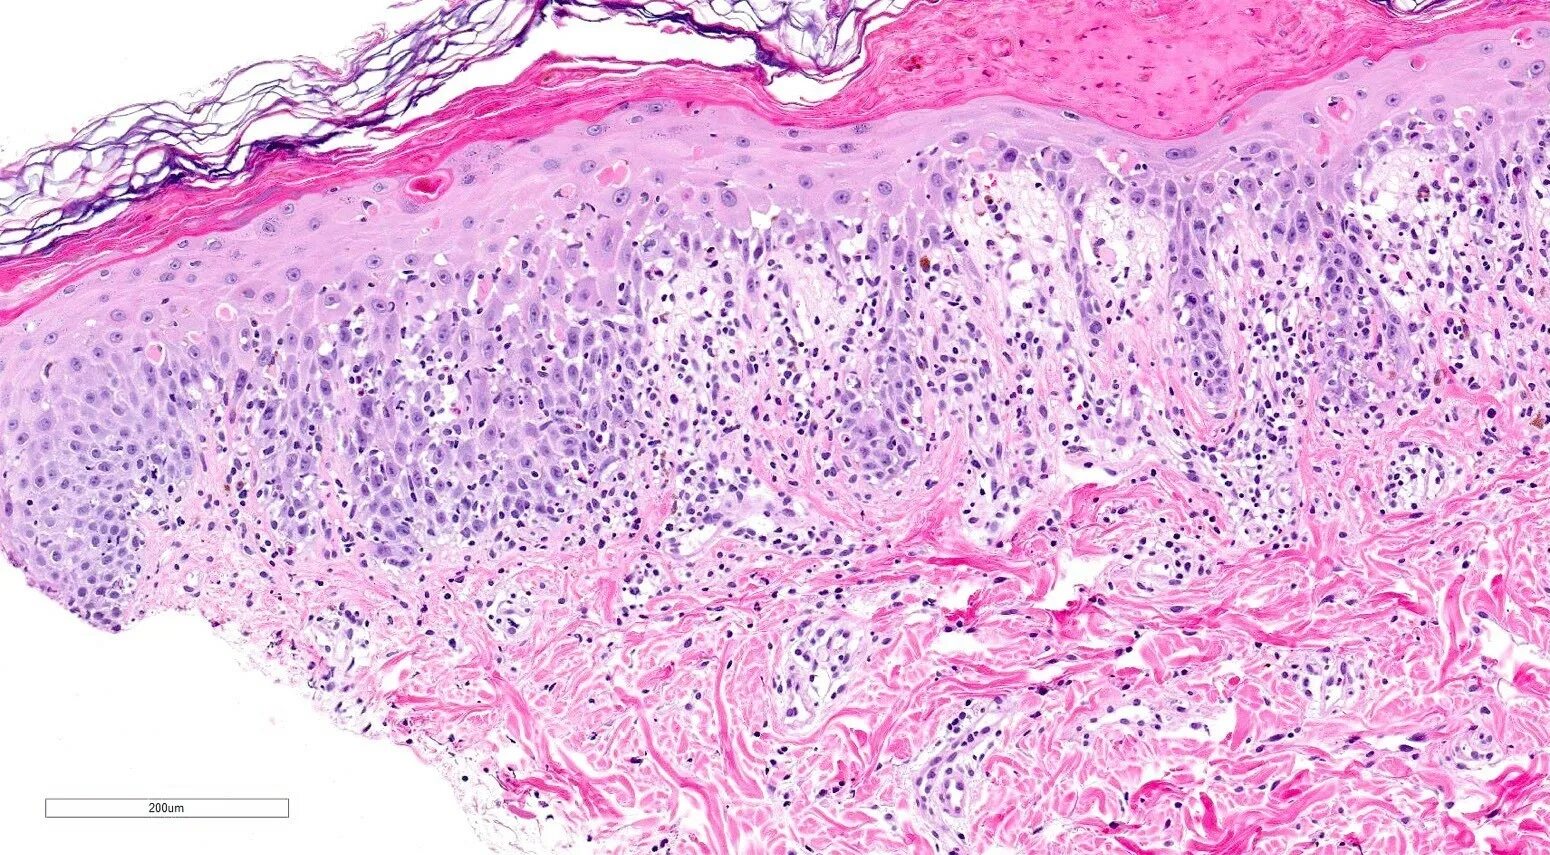

Что показала гистология замершей